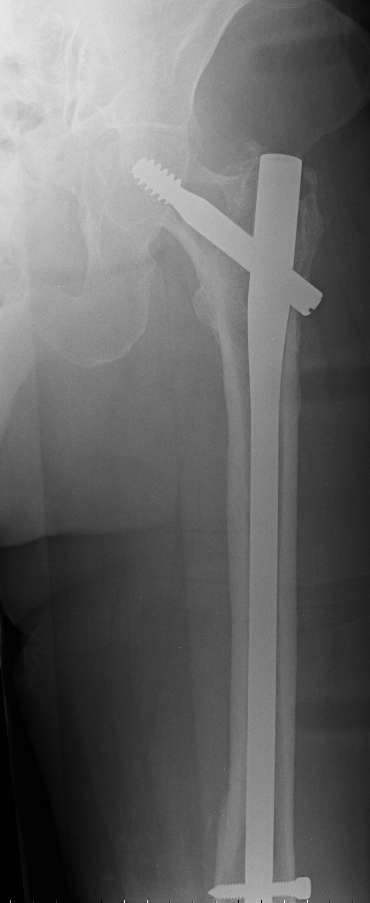

I should like know what is your preferred treatment for this fracture at

the tip of a long Gamma nail (on a healed subtrocantheric fracture : see

img).

The patient is a 81 years old lady with osteoporosis and important knee

arthrosis (as you can see).

Do you remove the nail or not? can we obtain a stable ostheosynthesis

with a plate without remove the nail?

Do you prefer to apply a plate or an endomedullary nail (along the old

way of gamma nail) to preserve joint motion?

It is justified to apply bone cement in the bone loss ?